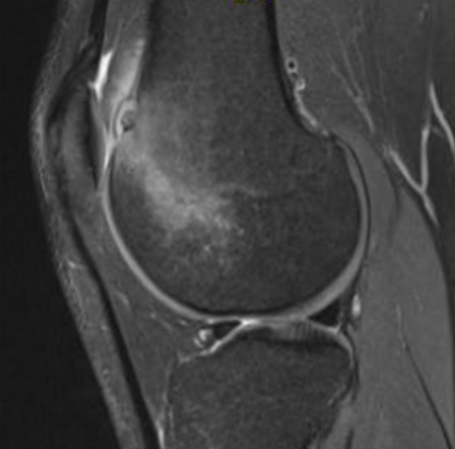

MRI

Osteoid osteoma femur